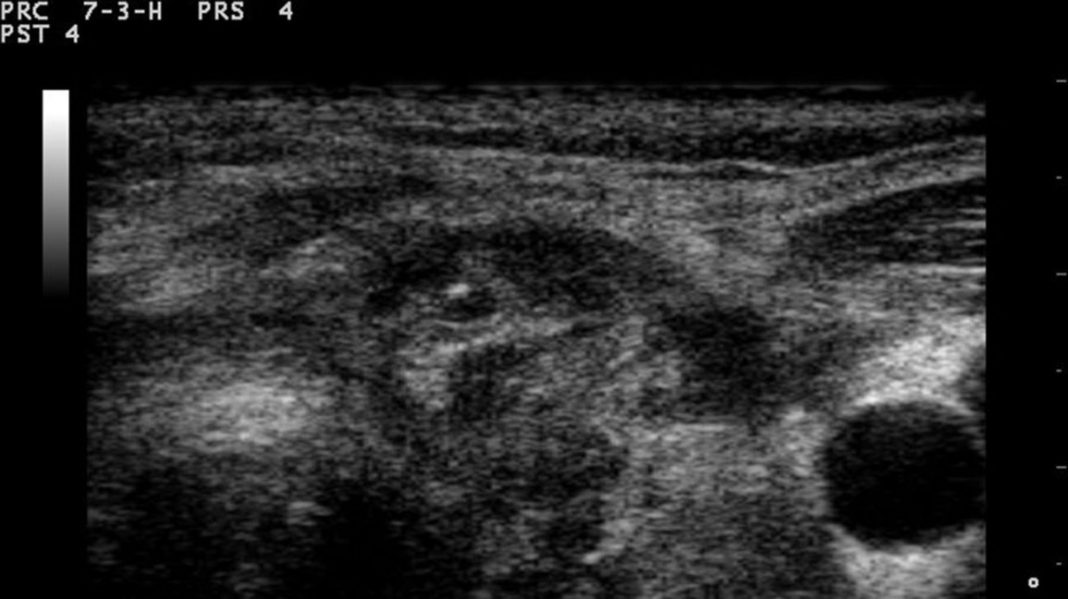

En el cuerpo se encuentra los ganglios y están en varias zonas importantes del mismo, estos pueden sufrir inflamación, y es muy común que sea en el cuello. Generalmente puede llegar a formar un bulto en el cuello, y se puede deber a alguna infección; sin embargo sea cual sea la razón hay que determinarla y controlarla para evitar problemas mayores.

En el siguiente artículo te explicaremos que son los ganglios, además de cuáles son las razones porque se presente un bulto en el cuello, para que su presencia puede ser diagnosticado a tiempo la causa y su posterior tratamiento también.